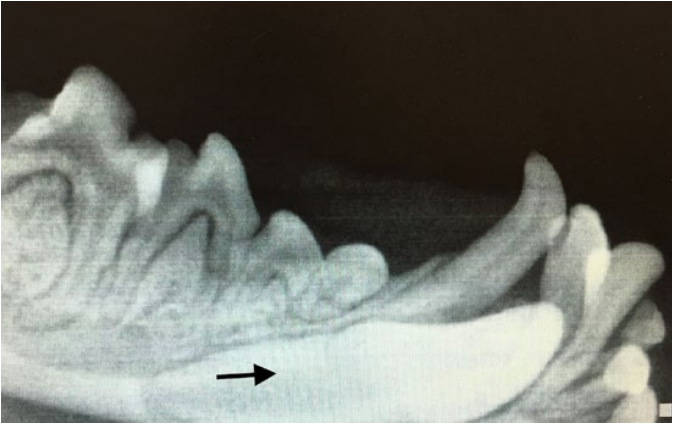

В случаях, когда постоянный зуб прорезывается неестественным путем или его зачаток располагается таким образом, что не может запустить процесс разрушения временного зуба, он прорезывается рядом. В результате смены зуба не происходит (за исключением процесса боковой резорбции, возникающей не на верхушке корня зуба, а на боковой поверхности временного корня, когда зубы находятся в плотном боковом контакте) (фото 1).